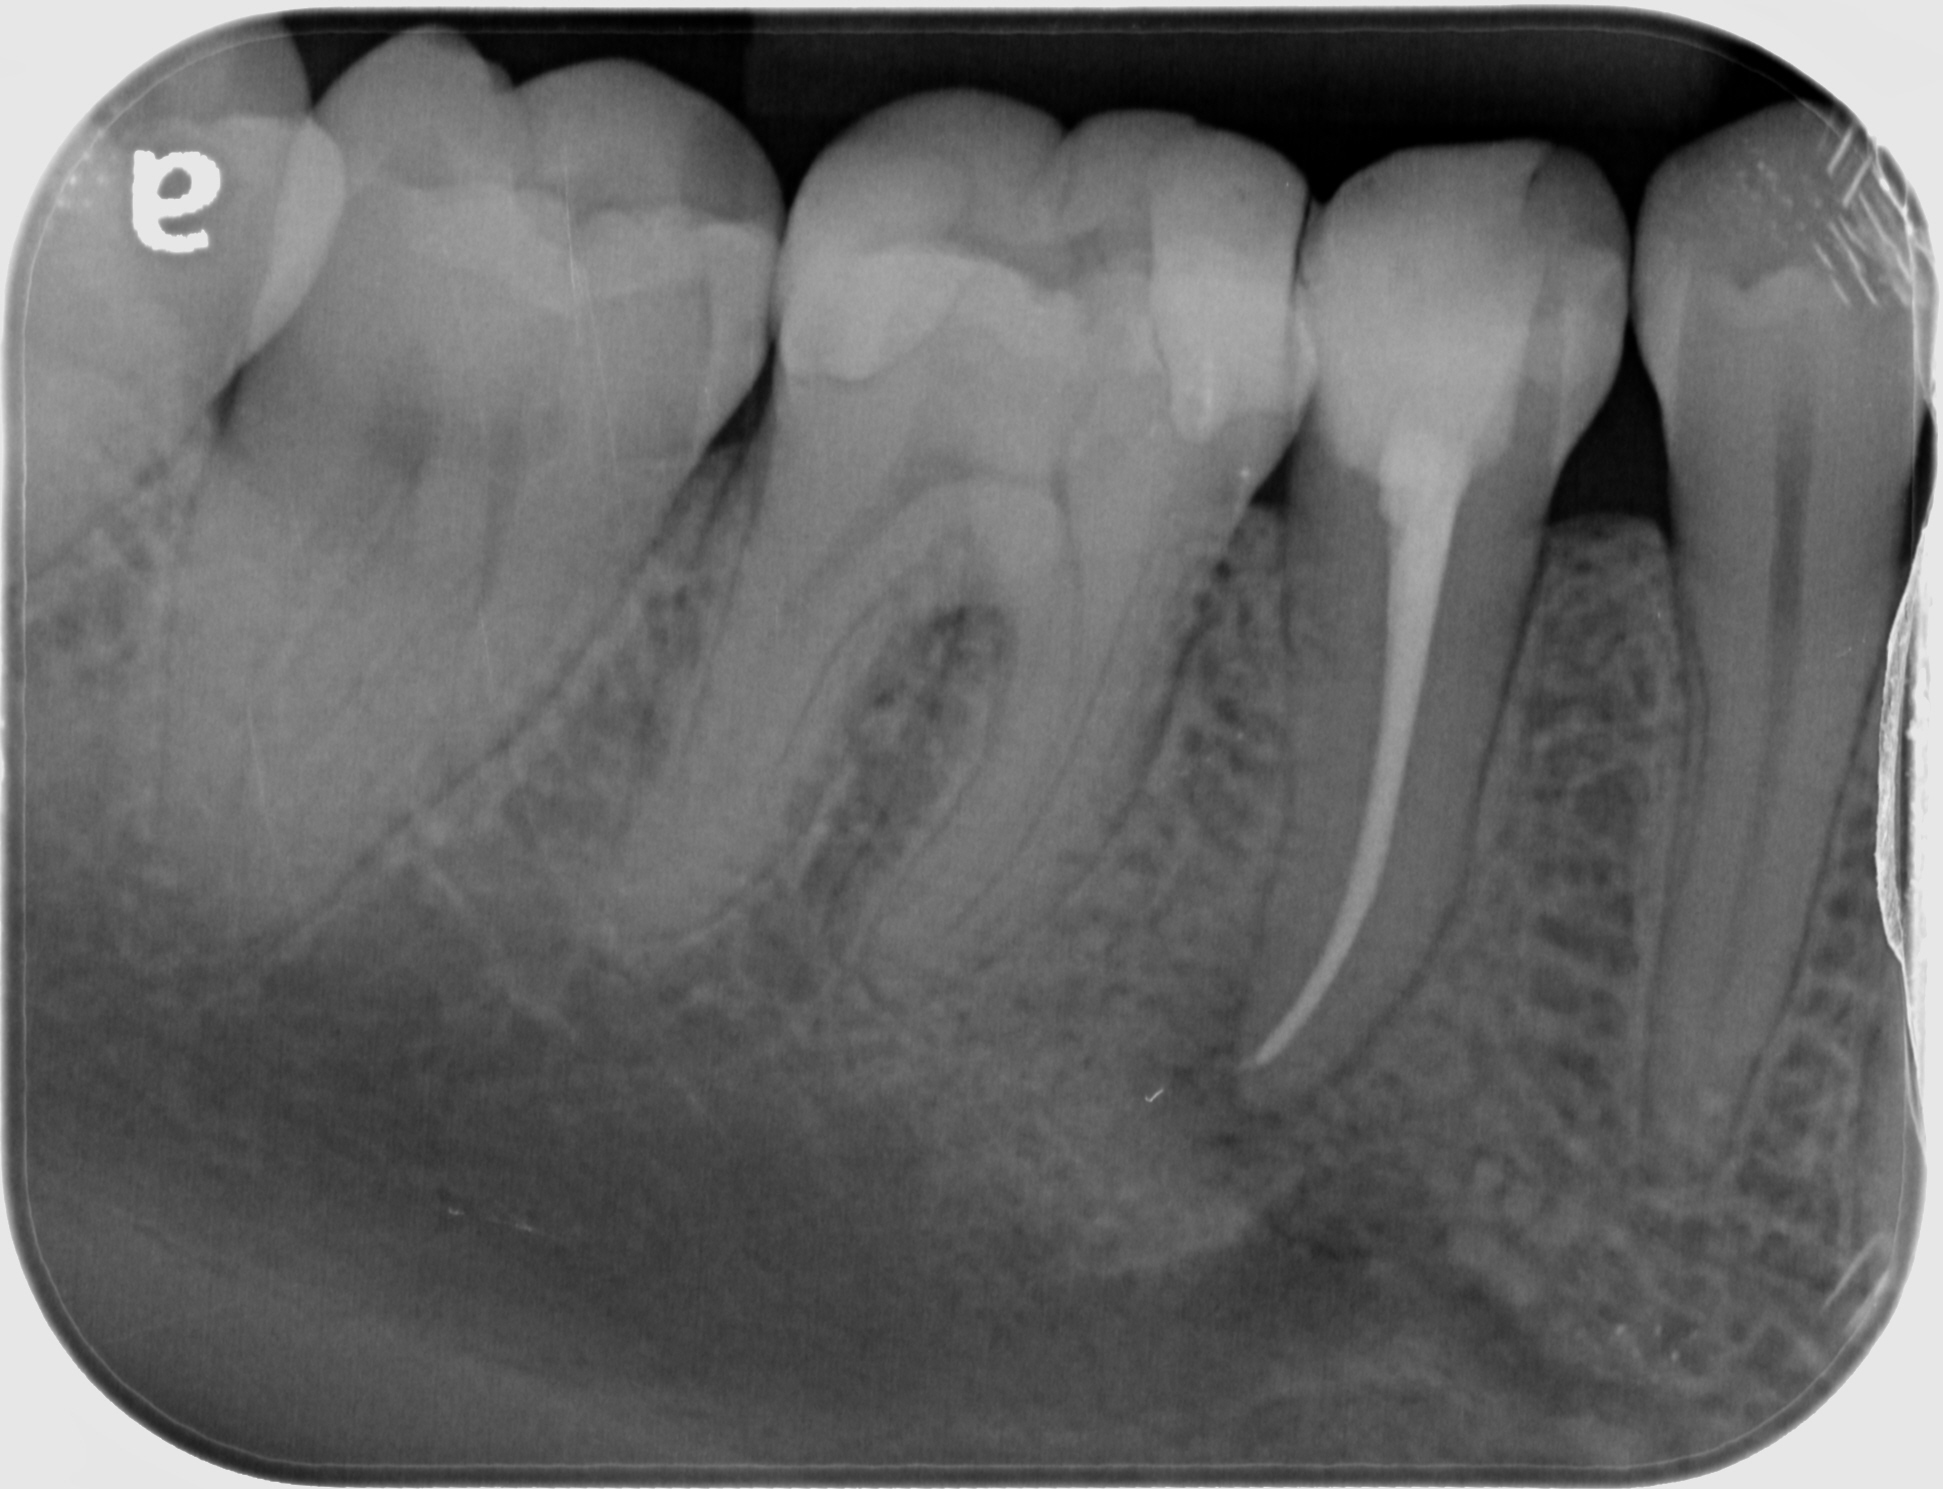

Root Canal Treatment in Maxillary First Permanent Molar 🟠 How to locate What Is Root Canal Filled With Root canal treatment, also known as root canal therapy or endodontic therapy, is a dental treatment for removing an infection. What is a root canal? — 6 min read. — root canal filling is the final step of any endodontic treatment. After the root canals are cleaned, shaped and. a root canal treatment is a dental procedure. What Is Root Canal Filled With.